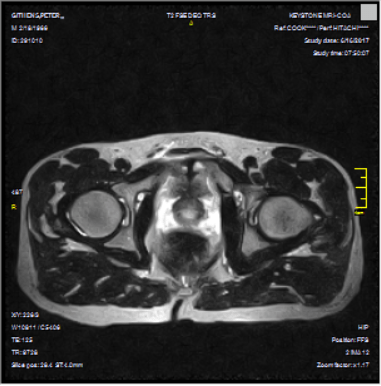

After all the testing and my prior visit with Vincera, I knew what the issues were and why I had constant, pulling discomfort in the groin and hip area. Contrary to the first MRI where it did seem as though I was going to give birth to

ET, the staff at Vincera had discovered a Core Muscle Injury (formerly known by me as athletic pubalgia, formerly known by all as the dreaded but poorly-named sports hernia.) Additionally, and perhaps causally, they found a fairly significant hip labrum tear in my left hip. Problem identified. Let’s fix it. I won’t re-bore you with the tale of insurance woes. Basically, I’m paying out of pocket to fix this.